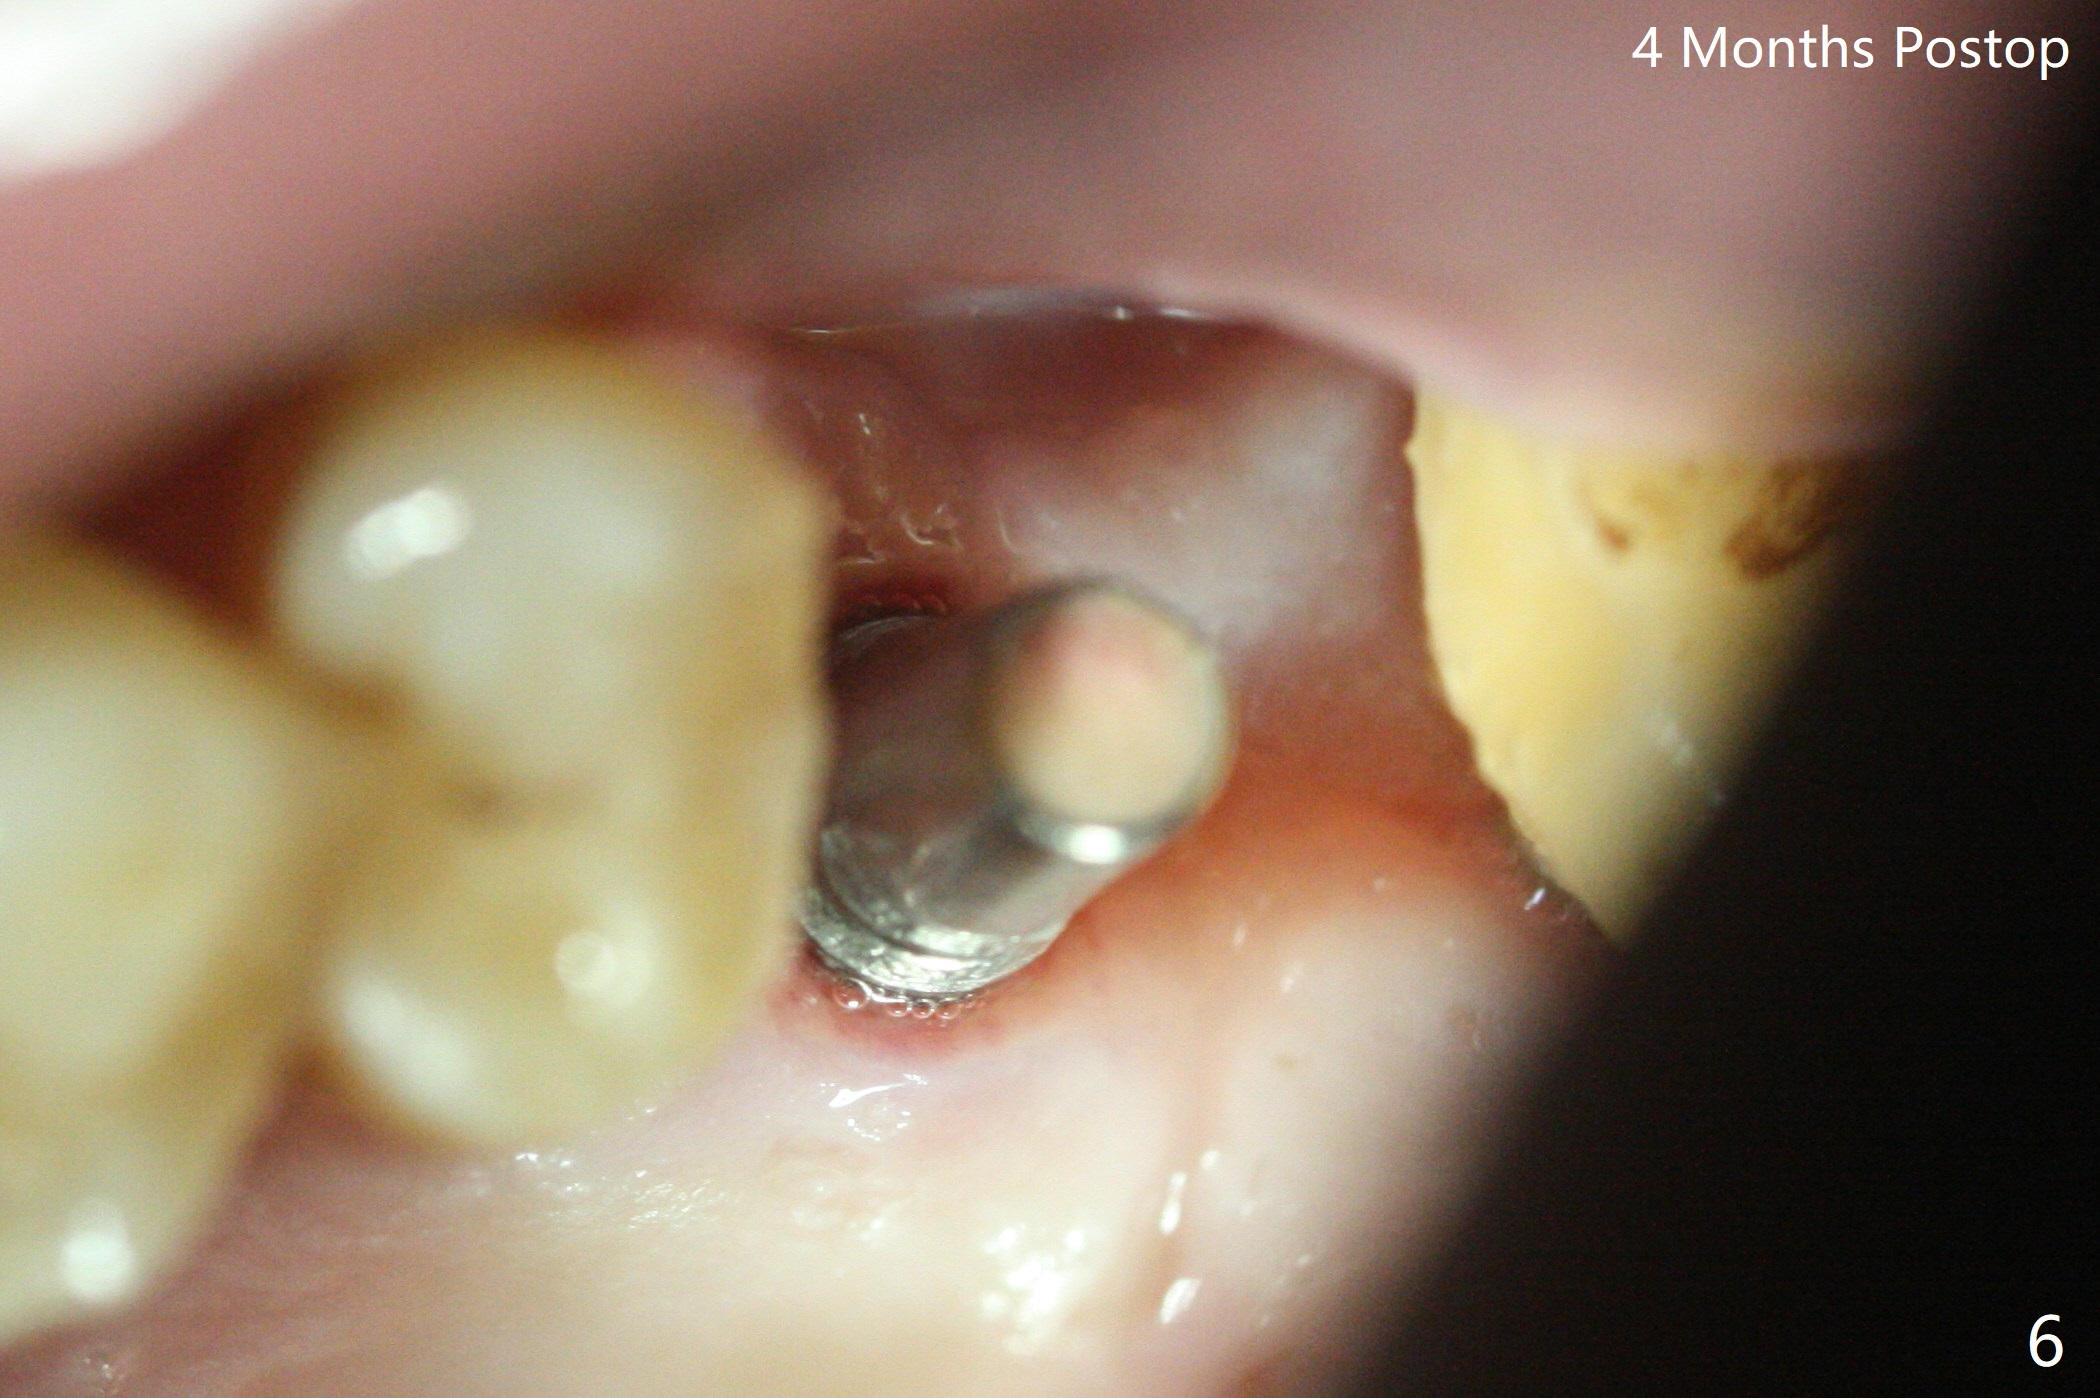

50岁男左上6严重斜型骨质吸收(意味着牙龈特别厚,有可能植入许多骨粉),拔除近中残根后,切开翻瓣,利用导板,4.5x11毫米植体不仅有意近中植入(补偿斜型骨质吸收而造成远中偏移),而且种得表浅(避免使用异常长的基台,改善冠根比例,图一),之后堆入不少粘性骨粉(图二:*),覆盖PRF膜,减张缝合(挺困难),牙周敷料。术后两周,敷料脱落,伤口裂开,但愿骨粉丢失不会太多(图三,四),树脂敷料可能更稳当。术后4个月骨粉好像覆盖远中曾经暴露螺纹(图五:^)。术后四个月伤口愈合(图六),临时牙冠大约3个月。粘固前局部牙龈健康,螺丝扭力30 Ncm。